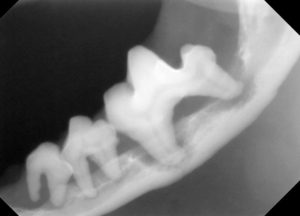

3.レントゲンでは、顎の骨が歯周病により骨折しやすい状態が確認されます。

4.下顎の顎先の骨も薄い状態です。

5.下顎の骨が溶けて、骨折しやすくなっています。